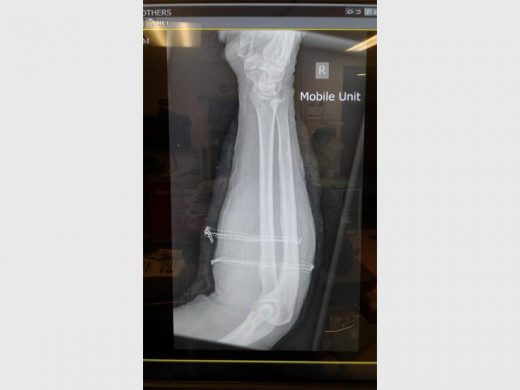

Kenny also said he is alive through the grace of the Lord. His right arm was shattered and he already had two operations to save some of his arm’s tissue and to remove some of the exposed flesh.

After the shooting, he was taken to Netcare Union Hospital where he spent the first three days in the Intensive Care Unit.

Kenny is still recovering at the Netcare Union Hospital and will undergo a third operation where doctors will do a skin graft.